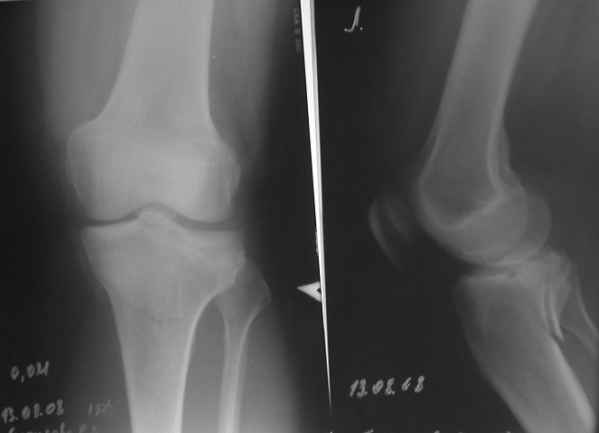

Действительно, доступ капризный. Из имплантов я бы выбрал Tomofix от синтез.